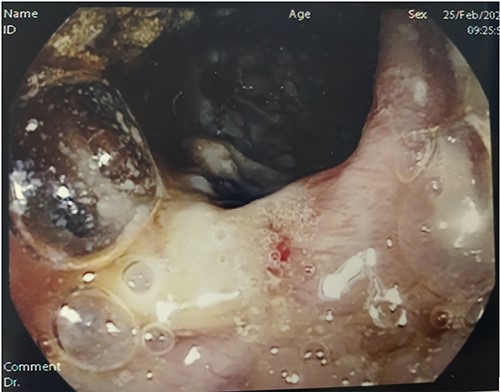

Histopathology of operative specimen. Panel A shows operating piece fixed with formalin: in panel A a large lymph node touched by disease is visible (asterisk). Panel B shows typical TB granuloma with caseation necrosis, lymphocytes, macrophages and also Giant cells. Panel C shows ulcer covered with fibrin and under granulation tissue. Under ulcer, there is caseation necrosis (arrow). Endoscopist should have to perform biopsies here to increase exam sensitivity.

ITB accounts for 1–3% of all TB cases worldwide. In the past, TB was thought to be associated with active pulmonary disease, but there is an increase evidence it can occur as a primary infection without evidence of pulmonary infection [1]. Among extra-pulmonary forms, intestinal involvement is less common than the one involving the genito-urinary tract, bone and meninges, yet it may cause significant morbidity and death. In a large retrospective study 6% of 66 034 admissions associated with tuberculosis had acute abdomen [2, 3]. Mycobacterium tuberculosis is the pathogen responsible for the majority of cases of ITB. Mycobacterium bovis is responsible for cases related to ingestion of infected dairy products. The principal route of infection is swallowing micro-organisms through sputum or contaminated liquids/food [4]. The mucosal layer of GI tract can be infected by bacilli forming epithelioid tubercles in the submucosa lymphoid tissue. Caseous necrosis of the tubercles, after 2–4 weeks, leads to ulceration of the overlying mucosa and it can later spread into the deeper layers, adjacent lymph nodes and into the peritoneum [5]. Mycobacterium can affect any region of the GI tract, even if the ileum and cecum are the most common sites. Various factors such as intestinal fluid stasis, presence of abundant lymphoid tissue, increased absorption rate at this site and close contact of the bacilli with the mucosa contribute to the terminal ileum infection [6]. ITB can manifest itself in three distinct phenotypes: ulcerative, hypertrophic and ulcerohypertrophic, with the ulcerative type being the most common. Ulcerative disease usually shows transverse ulcers often superficial and heal by fibrosis. Hypertrophic forms show thickening and a mass-like appearance of the bowel associated with scarring and fibrosis [1]. ITB can mimic other diseases including CD, as their clinical manifestations non-specific: the most common patient complaint is chronic abdominal pain. Clinical features are diarrhoea, haematochezia, perianal disease and extraintestinal manifestations, which point to CD diagnosis, whereas fever, night sweats, lung involvement and ascites indicate ITB diagnosis. Endoscopic features such as left colonic involvement, presence of longitudinal ulcers, aphthous ulcers, cobblestoning and skip lesions are more common in CD, whereas presence of transverse ulcers and patulous ileocecal valve are more common in ITB. Both CD and ITB are characterized by chronic granulomatous inflammation: both size and number of granulomas were higher in ITB than in CD. Giant cells, caseation necrosis, confluent granulomas and granuloma with lymphoid cuff were more frequently associated with ITB [7] (Fig. 4 panel B). Although caseation and necrosis in granulomas or positive stain for AFB is virtually diagnosis for ITB, the poor yield of endoscopic sampling results in the disease being diagnosed in <30% [8]. In CD, the endoscopist performs biopsies on the mucosa adjacent to the ulcerated mucosa; if ITB is suspected, biopsies should be carried out in the ulcerated area resulting from the underlying caseation necrosis (Fig. 4, panel C).